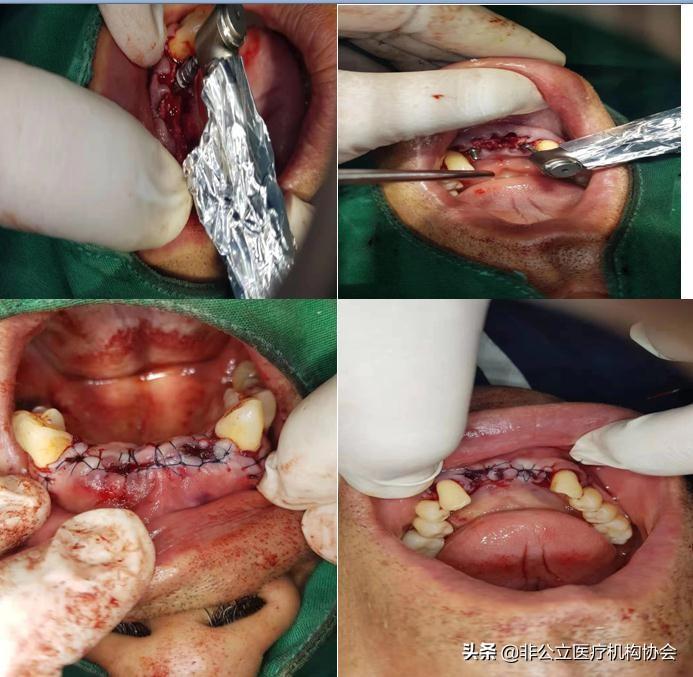

術前消毒(二)

患者術前的唇頰側觀(三)

患者術前病人的先拔牙(四)

新技術離心機抽血形成骨粉作用。

人工種植牙過程,很簡單,就要拔除牙齒一樣的。